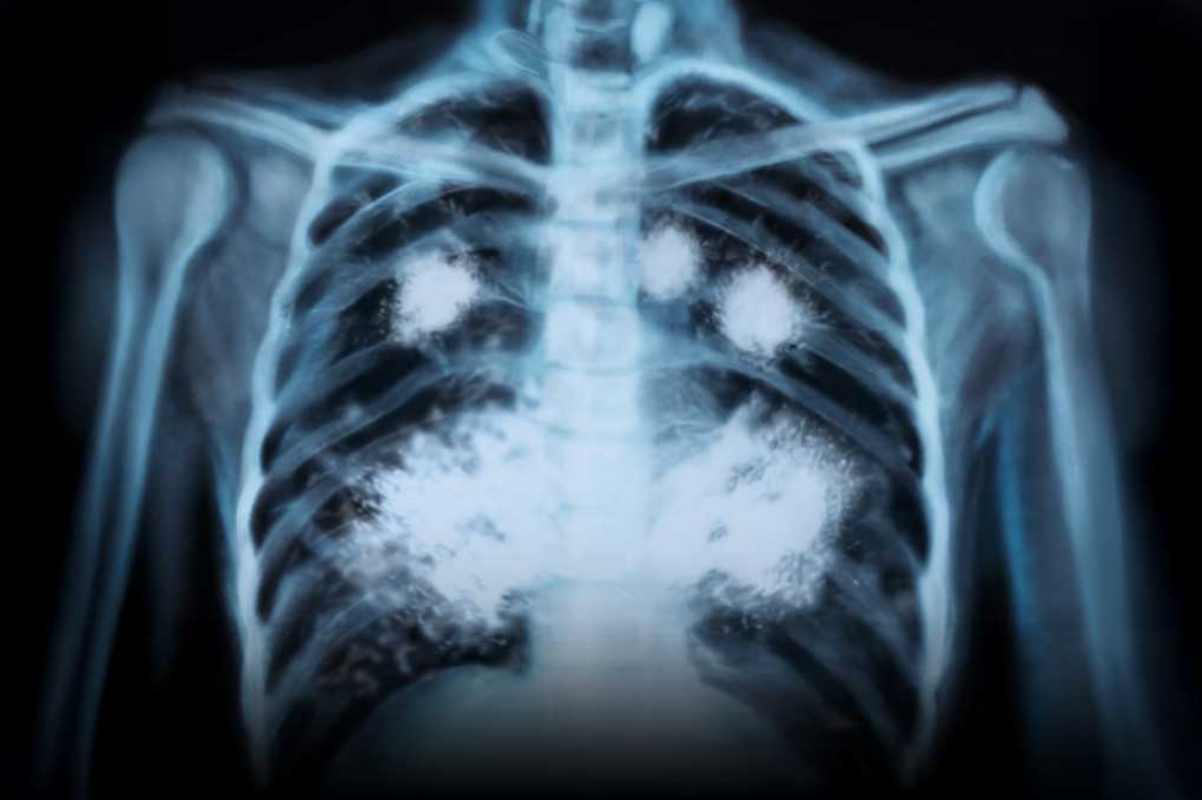

Un joven de 20 años fue al médico por una tos que no se le quitaba. Pensó que era algo leve, quizá gripe o alergia. Pero el diagnóstico lo sorprendió: sus pulmones mostraban el desgaste de alguien de 60 años.

Una de las enfermedades más preocupantes es la bronquiolitis obliterante, conocida como “pulmón de palomita”. Este trastorno cicatriza las vías respiratorias más pequeñas, impidiendo que el aire circule de forma normal. Los síntomas incluyen tos crónica, falta de aire, cansancio extremo y, en muchos casos, una vida limitada.

No hace falta una década de consumo para ver consecuencias: casos clínicos muestran que en tan solo dos años de vapeo pueden aparecer lesiones pulmonares comparables a las de un fumador de larga data.

Y no se trata de un caso aislado. Según la Sociedad Española de Neumología y Cirugía Torácica (SEPAR), miles de jóvenes ya presentan síntomas vinculados al vapeo, desde inflamación pulmonar hasta disminución de la capacidad respiratoria.